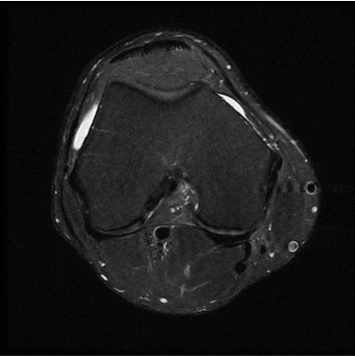

standard

384 x 256 (4 NEX)

3:02 minIAI (Innovative AI)

384 x 256 (2 NEX)

1:30 minReduced Scan Time

384 x 256 (2 NEX)

1:30 minstandard

384 x 256 (4 NEX)

2:59 minIAI (Innovative AI)

384 x 256 (2 NEX)

1:28 minReduced Scan Time

384 x 256 (2 NEX)